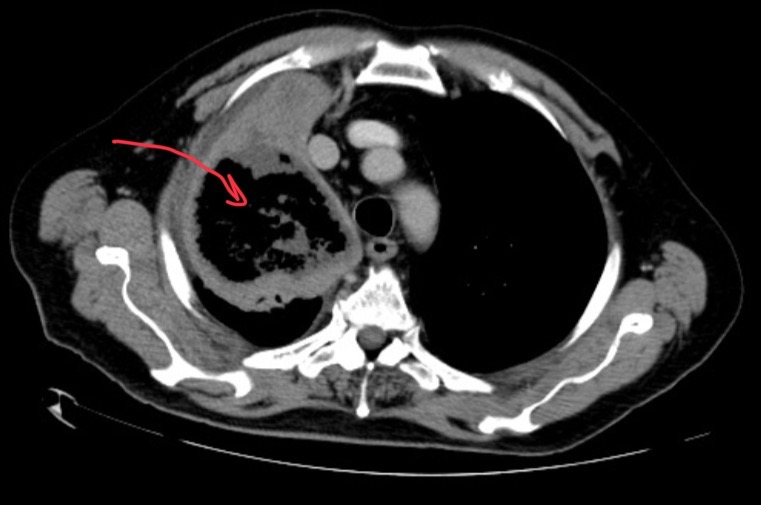

CT of pt

Shows pneumothorax in the right lung with mild plural fusion mediastinum push the left multiple mass lesions then the wild air density cyst surrounded by normal lung tissue.

Pt has tuberous sclerosis with lymphangioleiomyomatosis